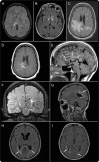

Neuromyelitis optica (NMO) is an inflammatory CNS syndrome distinct from multiple sclerosis (MS) that is associated with serum aquaporin-4 immunoglobulin G antibodies (AQP4-IgG). Prior NMO diagnostic criteria required optic nerve and spinal cord involvement but more restricted or more extensive CNS involvement may occur. The International Panel for NMO Diagnosis (IPND) was convened to develop revised diagnostic criteria using systematic literature reviews and electronic surveys to facilitate consensus. The new nomenclature defines the unifying term NMO spectrum disorders (NMOSD), which is stratified further by serologic testing (NMOSD with or without AQP4-IgG). The core clinical characteristics required for patients with NMOSD with AQP4-IgG include clinical syndromes or MRI findings related to optic nerve, spinal cord, area postrema, other brainstem, diencephalic, or cerebral presentations. More stringent clinical criteria, with additional neuroimaging findings, are required for diagnosis of NMOSD without AQP4-IgG or when serologic testing is unavailable. The IPND also proposed validation strategies and achieved consensus on pediatric NMOSD diagnosis and the concepts of monophasic NMOSD and opticospinal MS.